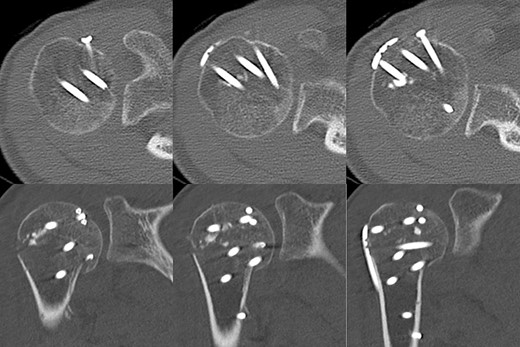

Postoperative radiographic and CT evaluations showed reduced fractures on the humeral head and surgical neck (Fig. 7). At 24 months of postoperative follow-up, radiographic and CT evaluations showed no signs of osteoarthritis or reimpression (Fig. 8). Two years after the primary surgery, we performed implant removal at the patient’s request (Fig. 9). When performing implant removal, we additionally performed a second-look evaluation with arthroscopy to assess the degree of healing in the joint. We noted no impression or exposure of cartilage callus on either side of the humeral head or glenoid (Fig. 10).

Two years later, pre-implant removal CT showed that the reduction in the depressed surface had been maintained with no obvious arthritic changes.